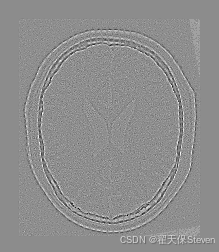

测试效果

官方给定的浮动图像在 X 轴方向偏移了 13 像素,Y 轴方向偏移了 17 像素,并旋转了10度,理想情况下配准结果应该接近这三个值。在实际运行中,优化器会找到最优的变换参数,输出类似如下的结果:

从结果可以看出,配准得到的平移量非常接近真实偏移量,说明配准算法成功地找到了最优变换参数。但也能看出仍存在一定位移偏差,官方也给出了解释,因为配准示例中采用了质心对齐的方法,而人为创造偏差时并不是这样处理的,所以整体的平移会有偏差。

过程图像如下:

配准前两图差值